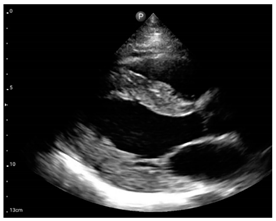

Compared to those who develop HFpEF, clinical HFrEF develops generally through disproportionate myocyte loss rather than hypertrophy (Figure 1) [49].

Figure 1.

Proposed mechanism for the progression of hypertensive heart disease to heart failure patterns, LVH: left ventricular hypertrophy, LV: left ventricular, HFpEF: heart failure with preserved left ventricular ejection fraction, HFrEF: heart failure with reduced left ventricular ejection fraction.